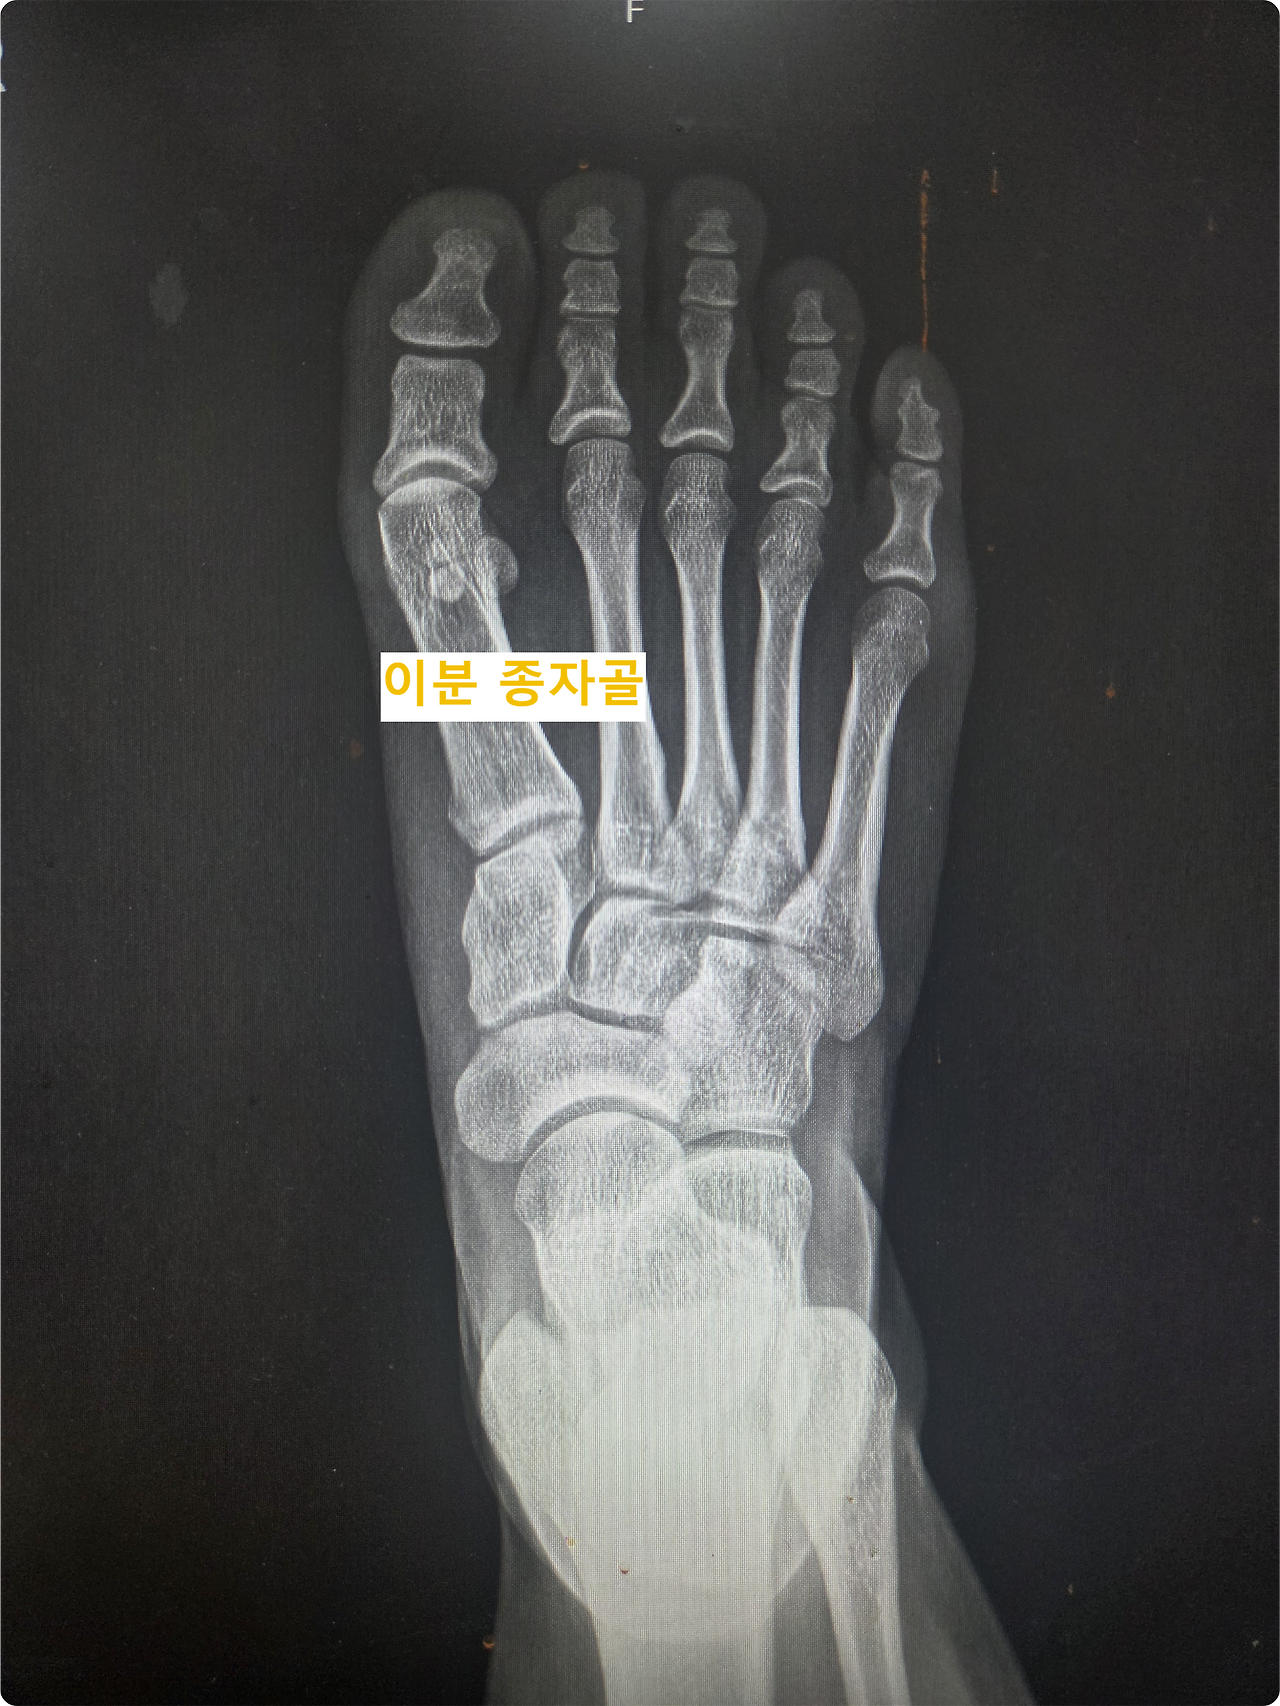

그가 처음 내 진료실을 찾은 것은 2024년 11월이었다. 당시 그는 이미 6개월 이상 엄지발가락 통증에 시달리며 여러 병원을 전전하던 상태였다. 깁스와 목발, 물리치료와 주사 치료까지 해볼 수 있는 건 다 해봤지만, 통증은 날카롭게 찢어지는 듯 심해졌고 보행조차 점차 어려워지고 있었다. 우선 시행한 X-ray 검사에서 통증 부위인 우측 종자골이 두 조각으로 나뉜 '이분 종자골' 형태가 확인되었다.

특이한 점이 있었다. 보통 이분 종자골은 80% 이상의 환자에서 양쪽 발 모두 관찰되는데, 이 환자는 유독 통증이 있는 우측에만 존재했다. 물론 한쪽만 이분 종자골인 경우도 드물지 않고, 환자의 직업 특성상 발에 충격이 잦아 '종자골염'일 가능성도 컸다.